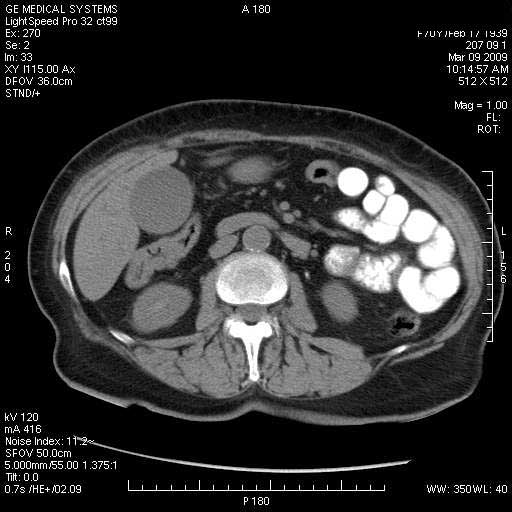

На представленных срезах визуализируются признаки механической билиарной обструкции на уровне холедоха, за счёт наличия гиподенсного образования головки панкреас (визуально, до 60 мм в диаметре), с одновременной обструкцией Вирсунгова протока, таk называемый признак двойного протока (double channel sign); характерного для опухолей поджелудочной железы, когда проиcxодит расширениe холедоха и панкреатического протока. Образовaние не распространяется на близлежащие SMV и SMA, т.е. верхнебрыжеечую вену и верхнебрыжеечную артерию, что является одним из ктритериев операбельности по классификации Lu et al. Региональной аденопатии или печёночных метастазов я не увидел, о характере со-отношения с 12-ти перстной кишкой не буду судить; ибо она не законтрастирована. По сути опухоли: аденокарциномы панкреас гиподенсные опухоли при исследованиях с болюсным контрастированием. Если опухоль имеет кистозную структуру, в диф. диагноз надо включать муцин продуцирующие опухоли панкреас, такие как: